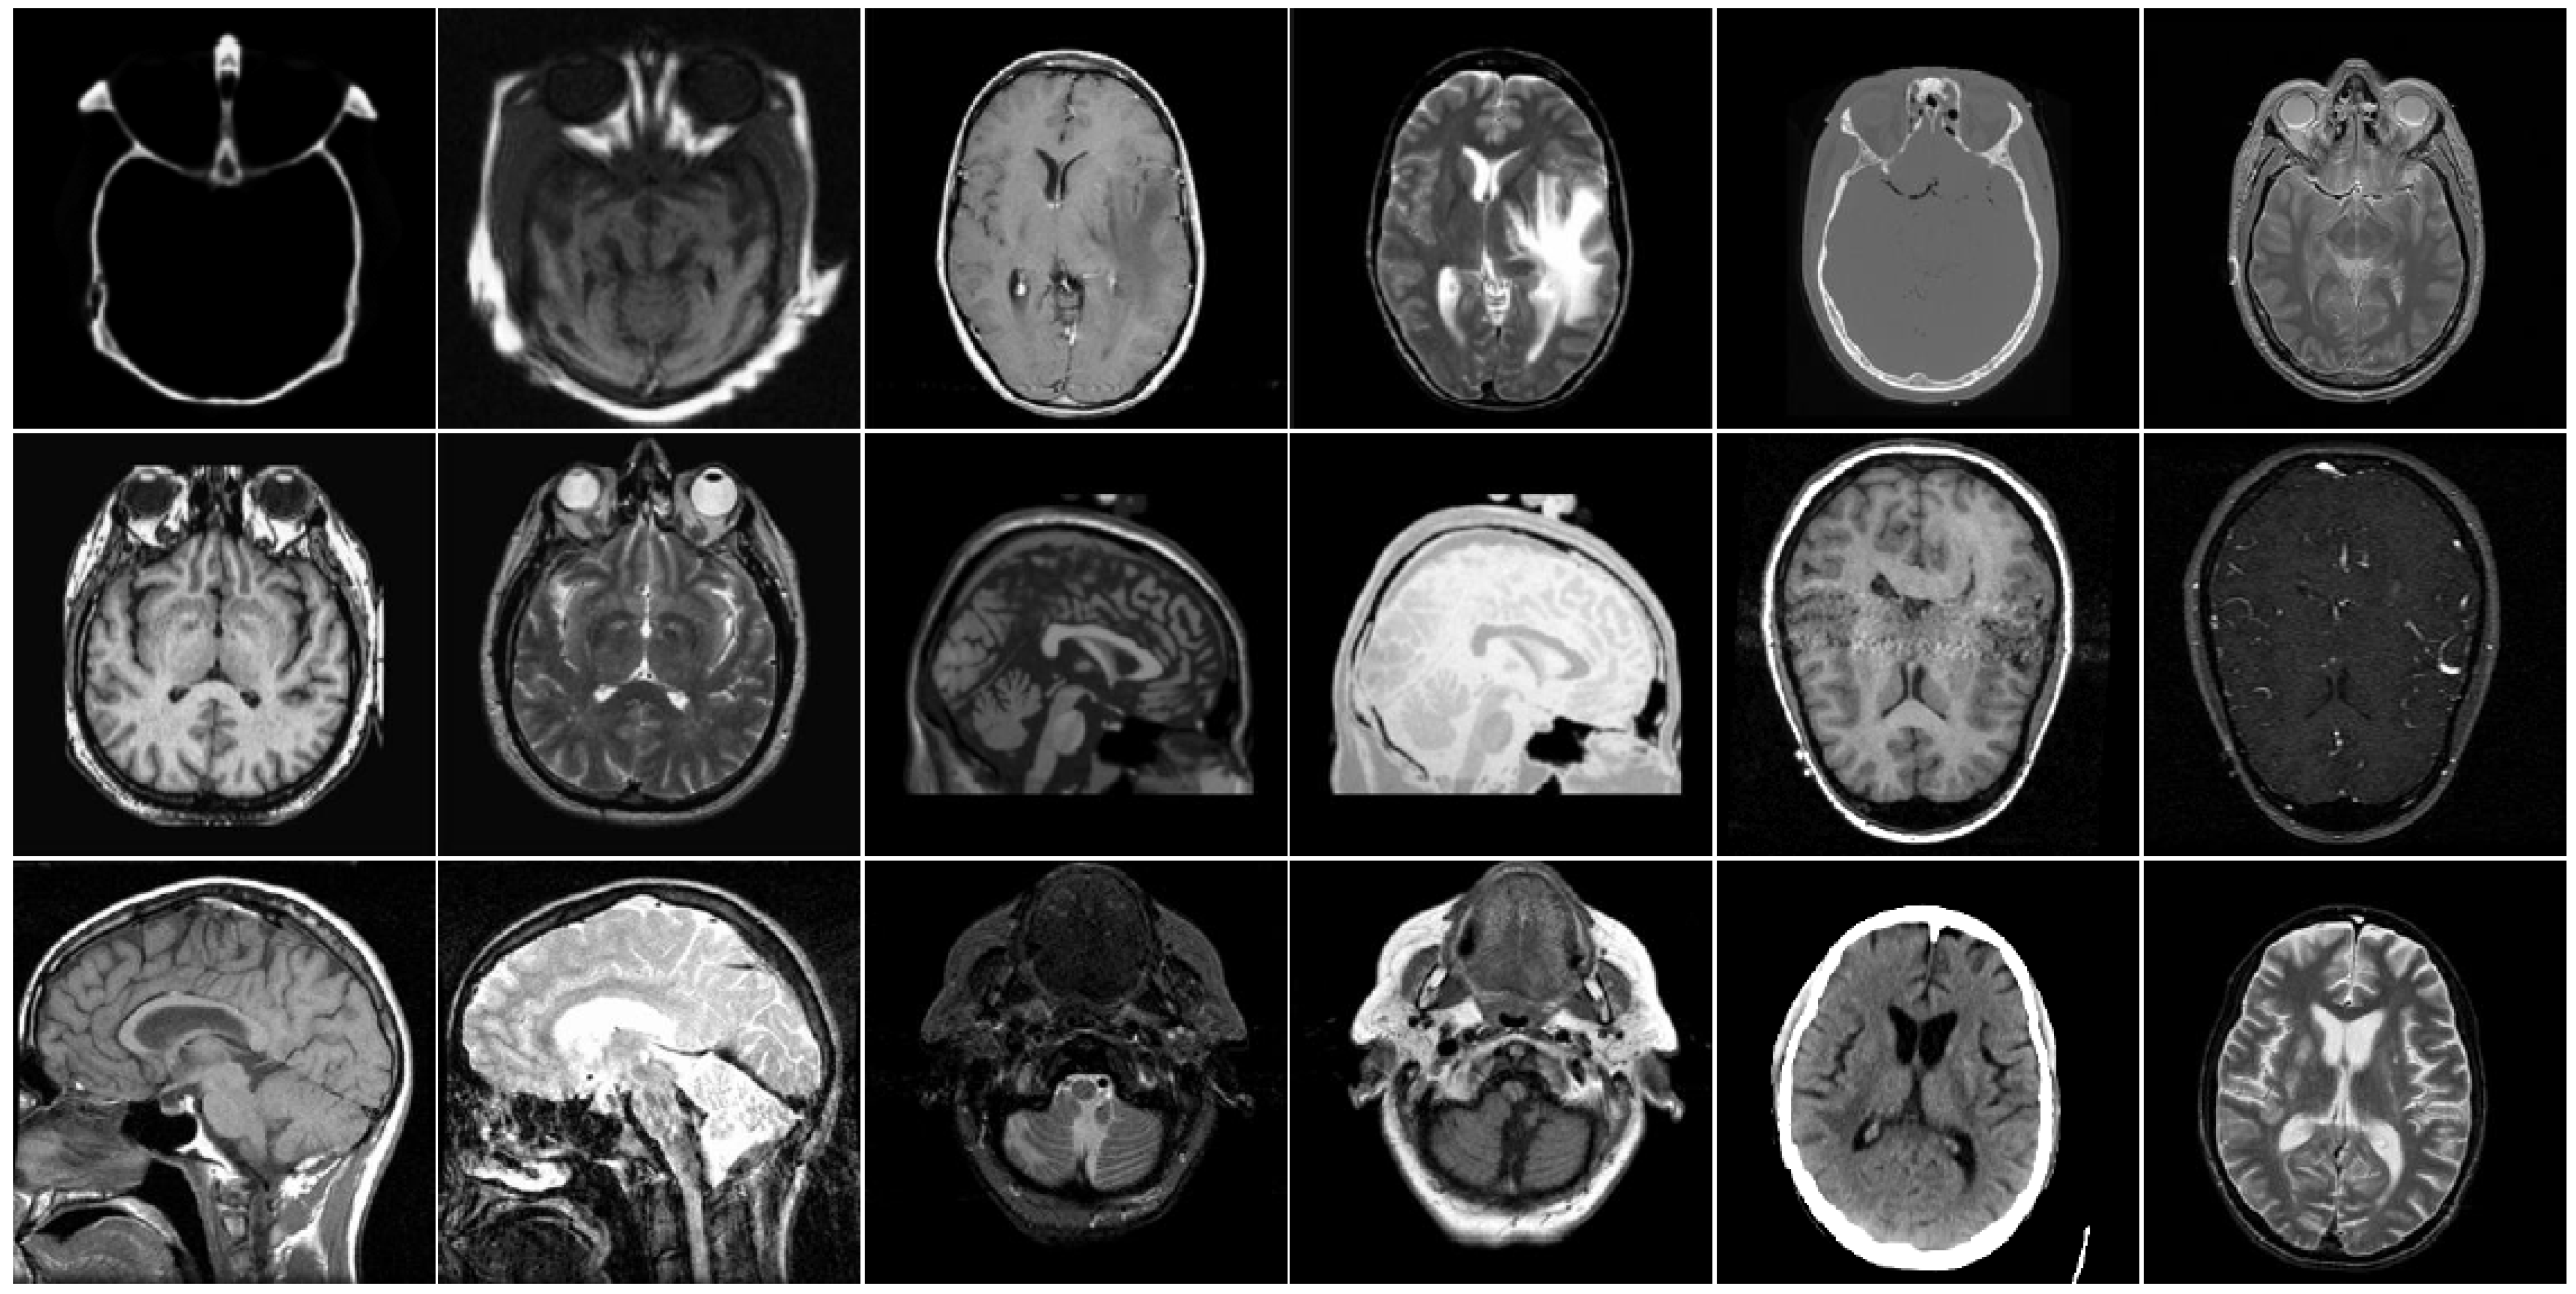

4.1. Experimental Setup

4.2. Comparison of Gray Image Fusion